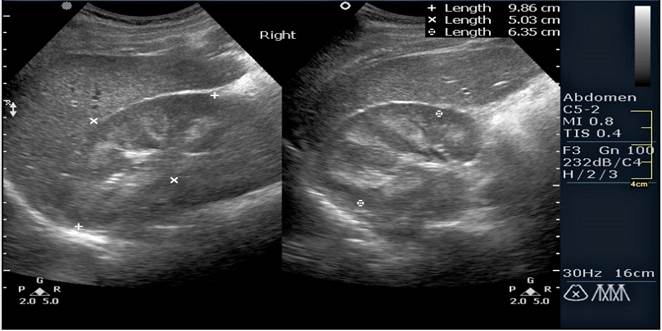

УЗИ – оң бү йрек 13, 8 х 5, 4 см, паренхима қ алың дығ ы 1, 4 см, біртекті, тостағ анша-қ алқ анша жү йесі 1, 6 см. Сол бү йрек 13, 5х5, 5 см, паренхима қ алың дығ ы 1, 4 см, тығ ыздалғ ан. Қ орытынды: екі бү йректің ө лшемдерінің ұ лғ аюы. Қ ұ рсақ қ уысындағ ы бос сұ йық тық.

Бү йректің УДЗ - н интерпретациялау Бү йректің биопсиясының мә ліметін интерпретациялау 1, 0 0, 5